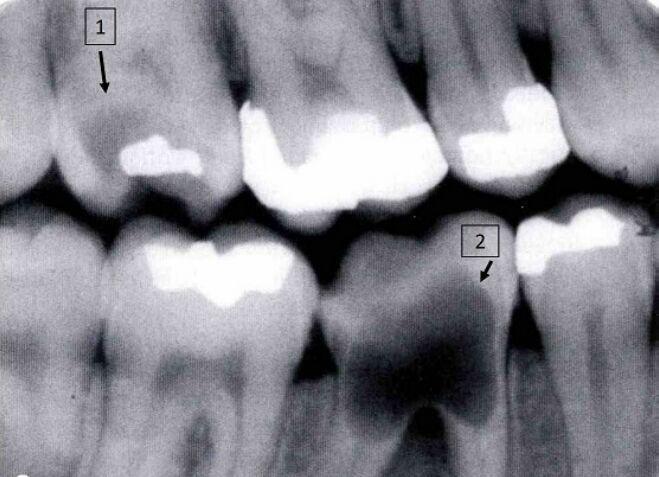

70.病患因右邊牙齒對冷熱食物刺激有疼痛感而來檢查,臨床檢查發現牙齒顏色變化,根尖X光片如附圖,標示1 與2處最可能的診斷為何? (A)1為齲齒(dental caries);2為內吸收(internal resorption) (B)1為內吸收(internal resorption);2為齲齒(dental caries) (C)1、2皆為齲齒(dental caries) (D)1、2皆為內吸收(internal resorption)

71.附圖之錐束電腦斷層掃描(cone beam computed tomography)片中,黑色箭頭所指牙齒異常為何? (A)咬耗(attrition) (B)磨耗(abrasion) (C)齲齒(dental caries) (D)內吸收(internal resorption)